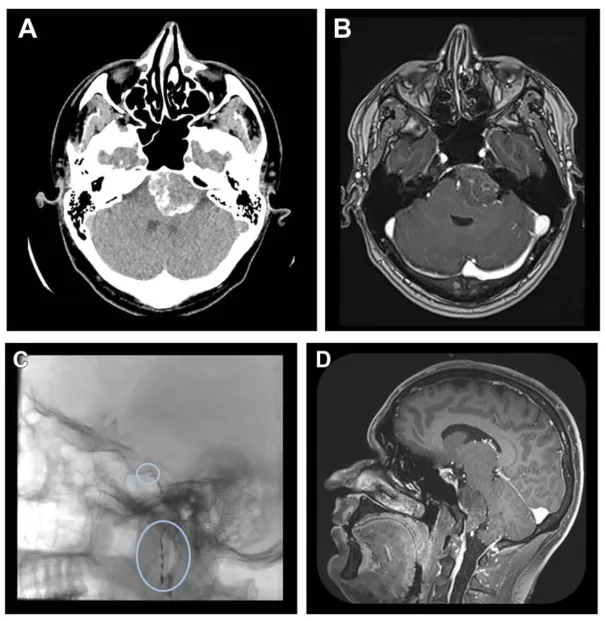

一名33岁男性因进行性加重的颈后部疼痛持续数月就诊。计算机断层扫描发现后颅窝有一枚钙化的轴外病变。磁共振成像确认为岩斜区脑膜瘤(29×39×38毫米),对脑桥和第四脑室产生占位效应,但未见脑积水。综合评估后,团队计划采用右侧单鼻孔经鼻入路进行手术切除。术前对咽升动脉和脑膜垂体干进行了栓塞,术后磁共振成像证实病灶成功去血管化。

图1. A和B,脑部计算机断层扫描及增强磁共振成像的轴位视图,显示一强化不均匀的低位左侧岩斜区脑膜瘤。C,术前咽升动脉和脑膜垂体干的栓塞。D,磁共振成像矢状位视图显示岩斜区脑膜瘤的部分去血管化。